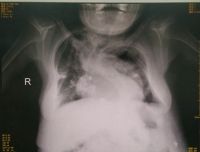

2017年11月,我院产科接诊了一名外院转诊的孕29周单绒毛膜双羊膜囊双胎妊娠且合并佝偻病、重度脊柱侧弯、严重肺部感染、孕前糖尿病、背部巨...